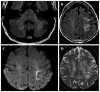

We describe common and less common diseases that can cause magnetic resonance signal abnormalities of middle cerebellar peduncles (MCP), offering a systematic approach correlating imaging findings with clinical clues and pathologic mechanisms. Myelin abnormalities, different types of edema or neurodegenerative processes, can cause areas of abnormal T2 signal, variable enhancement, and patterns of diffusivity of MCP. Pathologies such as demyelinating disorders or certain neurodegenerative entities (e.g., multiple system atrophy or fragile X-associated tremor-ataxia syndrome) appear to have predilection for MCP. Careful evaluation of concomitant imaging findings in the brain or brainstem; and focused correlation with key clinical findings such as immunosuppression for progressive multifocal leukoencephalopahty; hypertension, post-transplant status or high dose chemotherapy for posterior reversible encephalopathy; electrolyte disorders for myelinolysis or suspected toxic-drug related encephalopathy; would yield an appropriate and accurate differential diagnosis in the majority of cases.